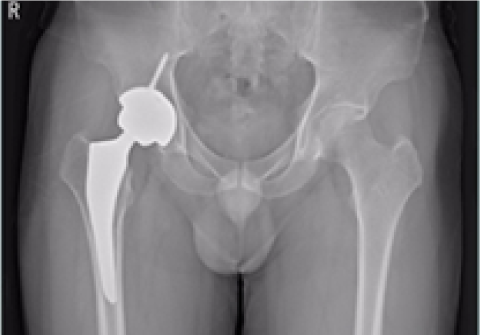

고관절 인공관절 부분치환술

2016.10.07

2017.02.09